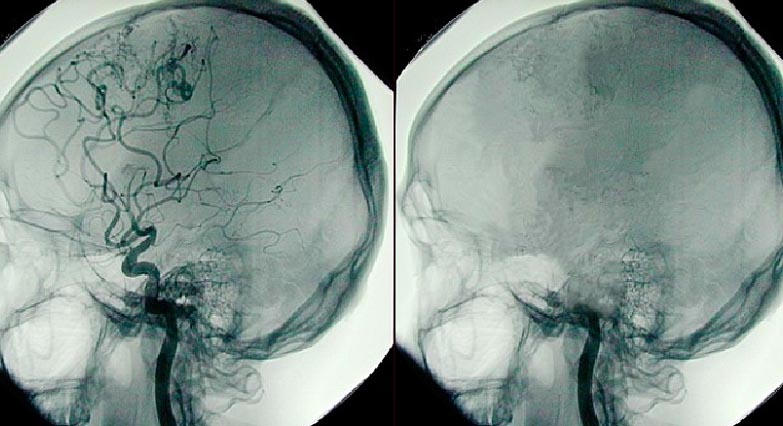

Ölüm anında neyronlar bağlandıqca beyində güclü elektrik dalğası yayılır. Bu elektrik dalğasına "anoksik depolarizasiya" deyilir və bu neyronların ölümünü göstərir.

Həkimlər dalğanın mənbəyini hədəf alaraq və ya yayılmasını məhdudlaşdırmaqla ölüm dalğasının qarşısını ala bilsələr, o zaman ölüm prosesini yavaşlatmağa və ya dayandırmağa kömək edə bilərlər.